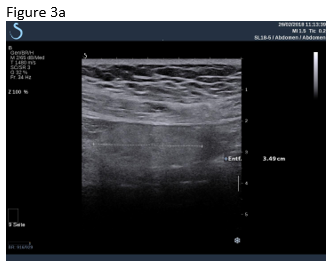

Figure 1: B-mode ultrasound using low frequency (a) and high frequency (b) revealed an isoechoic mass with a hypoechoic circumference. The mass was not adher-ent to the colon. Contrast enhanced ultrasound using low frequency (c) and high frequency (d) revealed that it was a non-enhancing segment of the omentum. Strain elastography showed that the lesion was stiffer than its sur-rounding tissue.

Figure 3: A follow up examination few weeks later revealed partially revascularised omental tissue in a now asymptomatic patient (a,b). Shear wave elastography is shown where there is now only relatively soft (inflammatory) tissue (c).